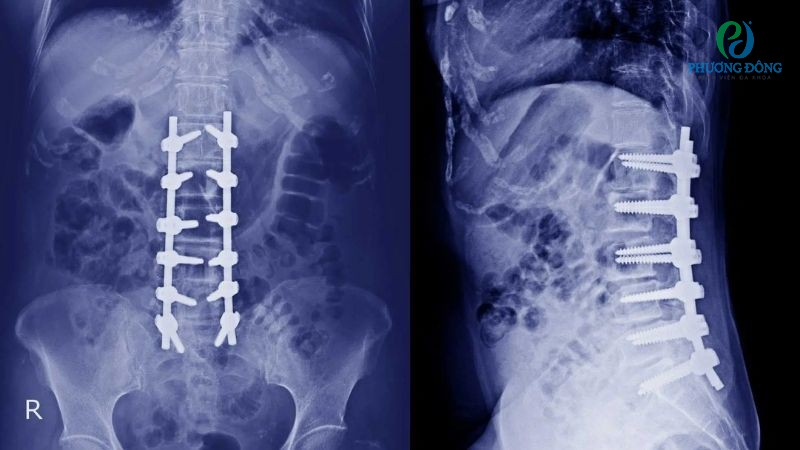

Hướng điều trị thông thường bao gồm dùng thuốc giảm đau, vật lý trị liệu, xoa bóp, bấm huyệt, châm cứu hoặc tập phục hồi chức năng chuyên biệt. Với trường hợp nặng hơn, bệnh nhân cần can thiệp ngoại khoa như thay đĩa đệm nhân tạo, nội soi xử trí tình trạng chèn ép.